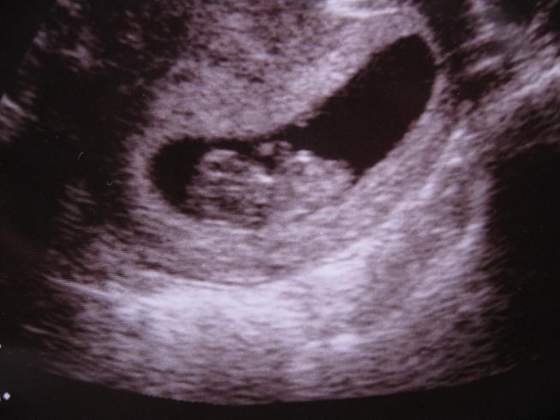

witam przeczytałam już wszystkie strony archiwalne więc teraz i ja postanawiam dołączyć do was kochane mamuśki. Dodam mojego bąbelka 11 tygodniowego mierzącego 3,5 cm od główki do "dupci" (martwię się czy oby nie za mało mierzy?) :-(